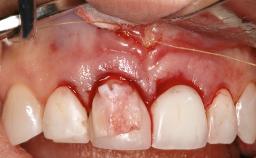

Reconstructive Treatment of a Peri-Implantitis Defect at an Implant in a Mandibular Molar Site

In this case, Mario Roccuzzo utilizes surgical bone regeneration treatment around implant 46 using a bone graft substitute and a connective tissue graft to resolve peri-implant inflammation, reduce the probing depths, and prevent further progression of disease.

A 58-year-old-male patient was referred in February 2007 for implant placement in the right mandibular molar area. Two tissue level implants were inserted at sites 44 and 46, respectively, to support a three-unit fixed dental prosthesis (FDP).